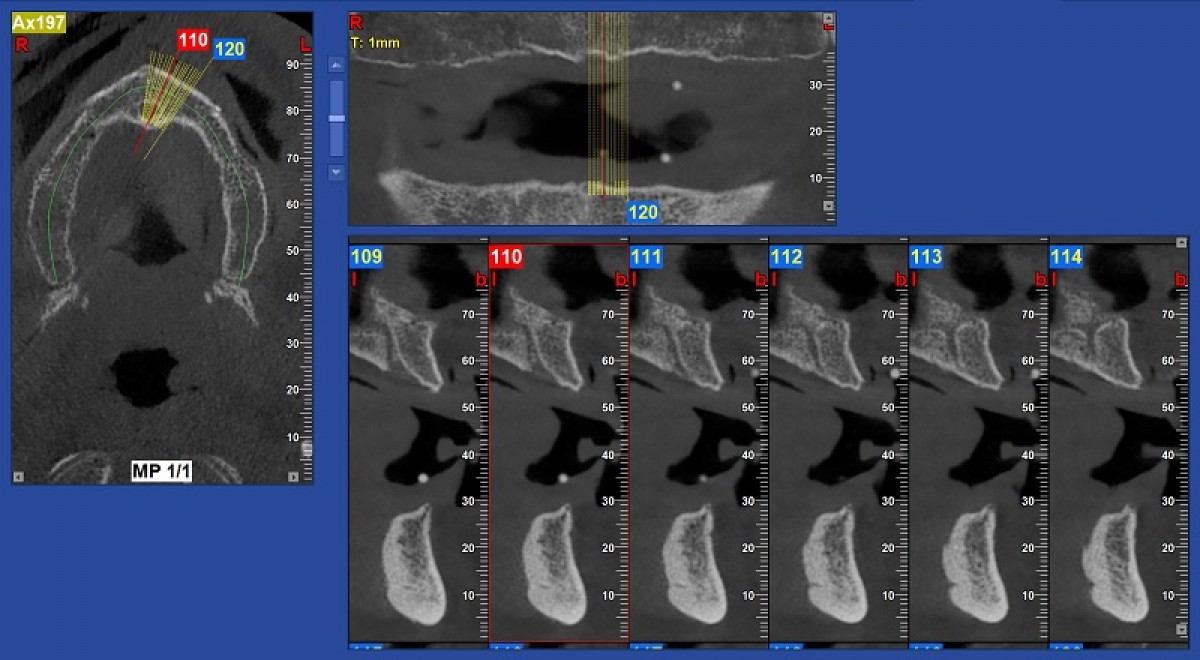

The cephalometric VTO allowed us to identify the exact movements the incisors need to make in the sagittal and vertical planes. To complete the three-dimensional treatment planning, the virtual set-up was used. The dental arches were further scanned using the Trios (3Shape) scanner (fig. 6).

The intraoral scan file was then uploaded to the Insigna (Ormco) web application where the arches were segmented (i.e. the teeth were separated from each other) and an initial virtual set-up was performed by Insigna technicians. Subsequently - again on the Insigna web application - we perfected and completed the virtual set-up. The settings for the position and the angle of the upper and lower incisors were based on the cephalometric VTO values (fig. 7).